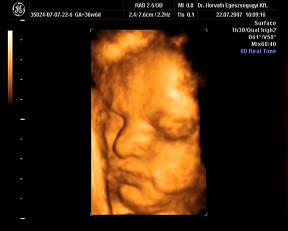

ma megvolt a -ha minden igaz- utolsó ultrahang. Nagyon jó volt, kisit furcsa érzés, hogy Ákossal már nem megyünk ilyenre...de nemsokára gyönyörködhetek benne állandóan 4D-ben-hanggal:D:D:D

Nagyon jól van, hála Istennek, csinált adoki flowmetriát is-az is rendben teljesen. A súlya 2870 gramm-ideális, a méretei a korának megfelelőek. A doki azt mondta, úy készüljek, hogy maximum két hétvégém van még az Urammal kettesben:D:D:D Nagyon várom már!!

Rakok náhény képet:

édes kis grimaszai vannak, nem? :oops: